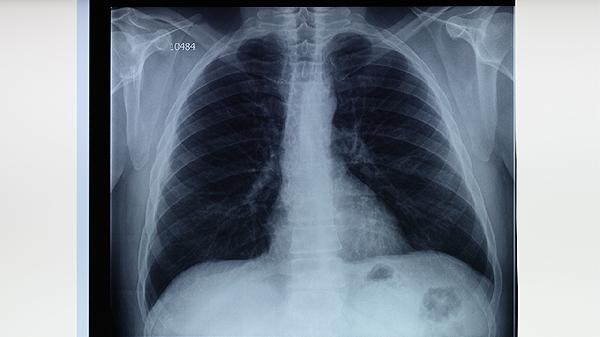

抗结核药物通常需要2-4周才能显著缓解症状。结核分枝杆菌生长缓慢,药物抑制细菌繁殖后,肺部炎症消退需要时间。服药初期可能出现持续低热、咳嗽、乏力等症状,属于治疗过程中的常见现象。部分患者对利福平、异烟肼等一线药物敏感度较低,导致症状改善延迟。痰涂片检查可帮助评估治疗效果,胸部影像学变化往往滞后于临床症状。

少数患者存在原发耐药或获得性耐药问题,导致标准治疗方案效果不佳。基因检测可发现耐多药结核菌株,此时需调整为二线药物如阿米卡星注射液、左氧氟沙星片等。合并支气管扩张、真菌感染等情况也会延长症状持续时间。糖尿病患者血糖控制不佳可能影响抗结核药物疗效。免疫缺陷患者因机体清除病原体能力下降,症状缓解更为缓慢。